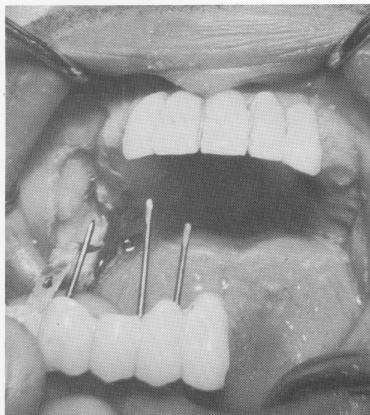

Fig. 4-39. The vent-plant unit remained firm in the bone.

Fig. 4-40. After severing the unit, it was easy to remove the nasal septum vent-plant.

4 Endosseous vent-plant implant unit is firm in the bone

5 Unit severed, nasal septum vent-plant implant removed